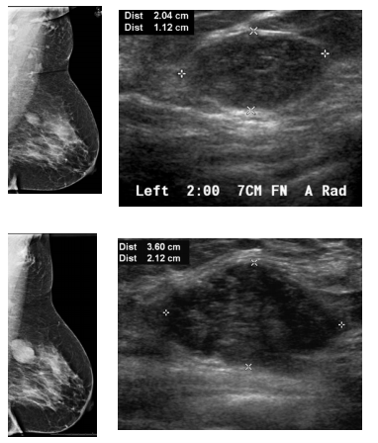

Breast Hamartoma.

“Breast within a breast”, or “sausage appearance”

NF-1 in an 80-yearold woman with multiple superficial neurofibromas over her torso. Right and left MLO mammograms (a) and left craniocaudal mammogram (b) show numerous dense, circumscribed ovoid masses surrounded by lucent halos of air in the axillae (arrowheads in a) and breasts (arrows in b), findings that represent cutaneous neurofibromas.